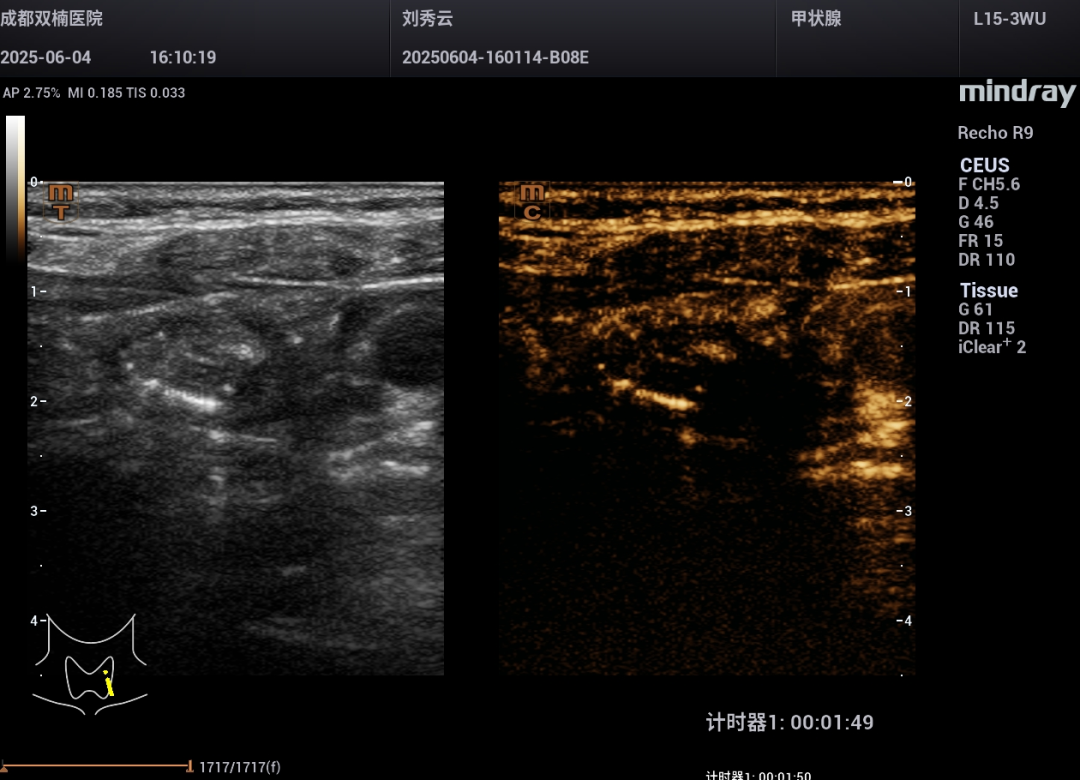

为进一步确认,程主任让刘阿姨喝下“一杯水(在400ml普通饮用水里只加了6滴造影剂)”。屏幕上清晰地显示:水流直接流入了那个“团块”里面!还发现“团块”靠近食管的部位有个小缺口。

饮造影水109秒